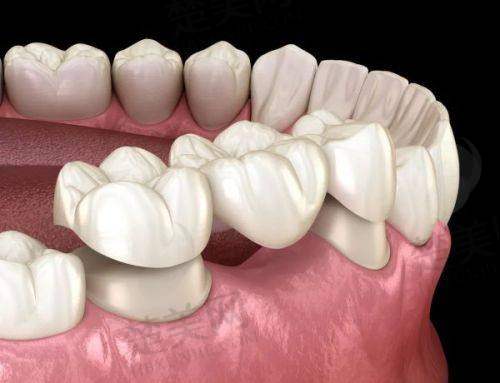

口腔美学修复也是该诊所的特色之一。雅美口腔作为老牌口腔医院,在口腔美学修复方面做到了精益求精。医生可以根据顾客的面部形态以及咬合关系,制定更加合适的修复方案。无论是牙齿的美白、清洁,还是根管治疗等,都能结合美学理念,让患者在治疗口腔疾病的同时,也能获得美观的牙齿外观。